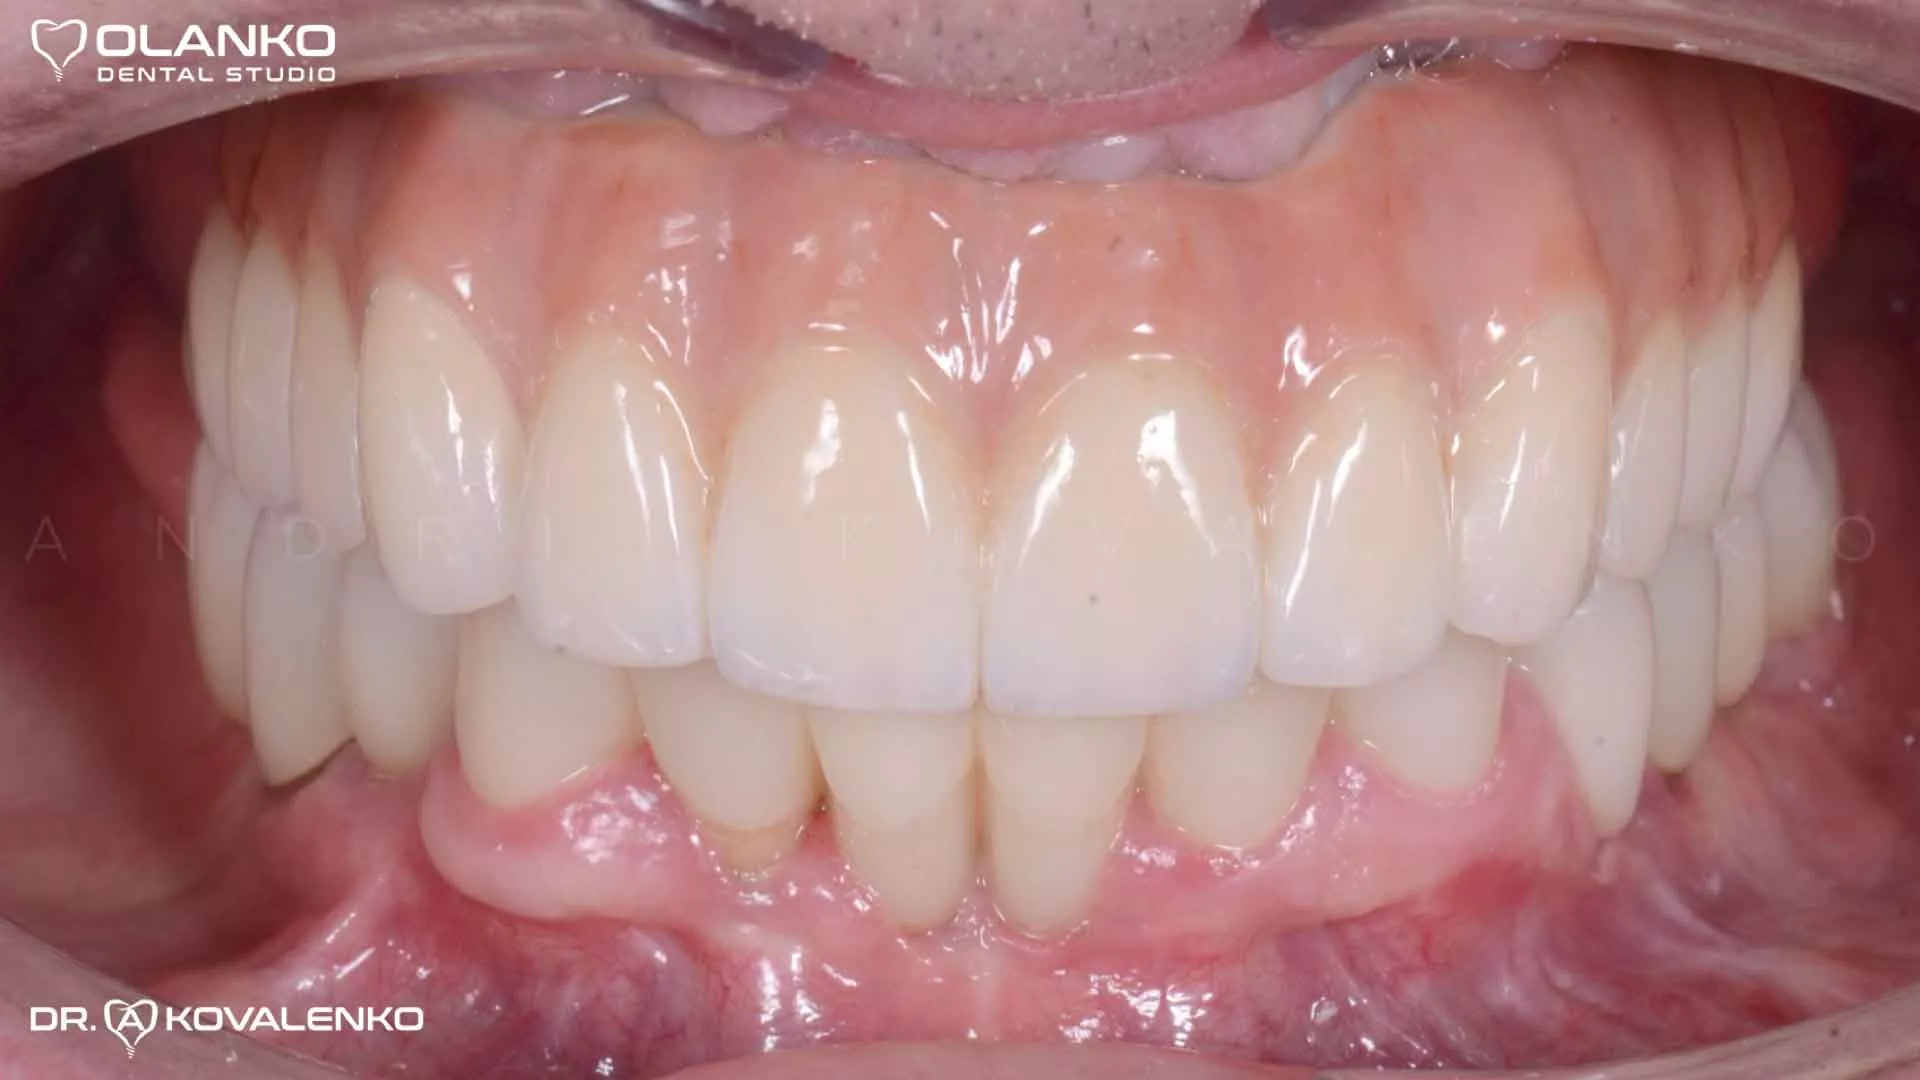

Фото  ПОСЛЕ фиксации работы в полости рта

Фото улыбки пациента ПОСЛЕ окончания лечения